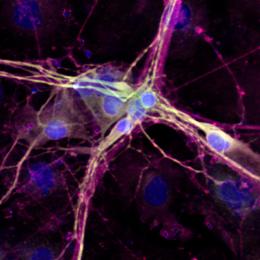

BrdU标记的神经细胞,该化学物质会引起一些不可预测的问题。